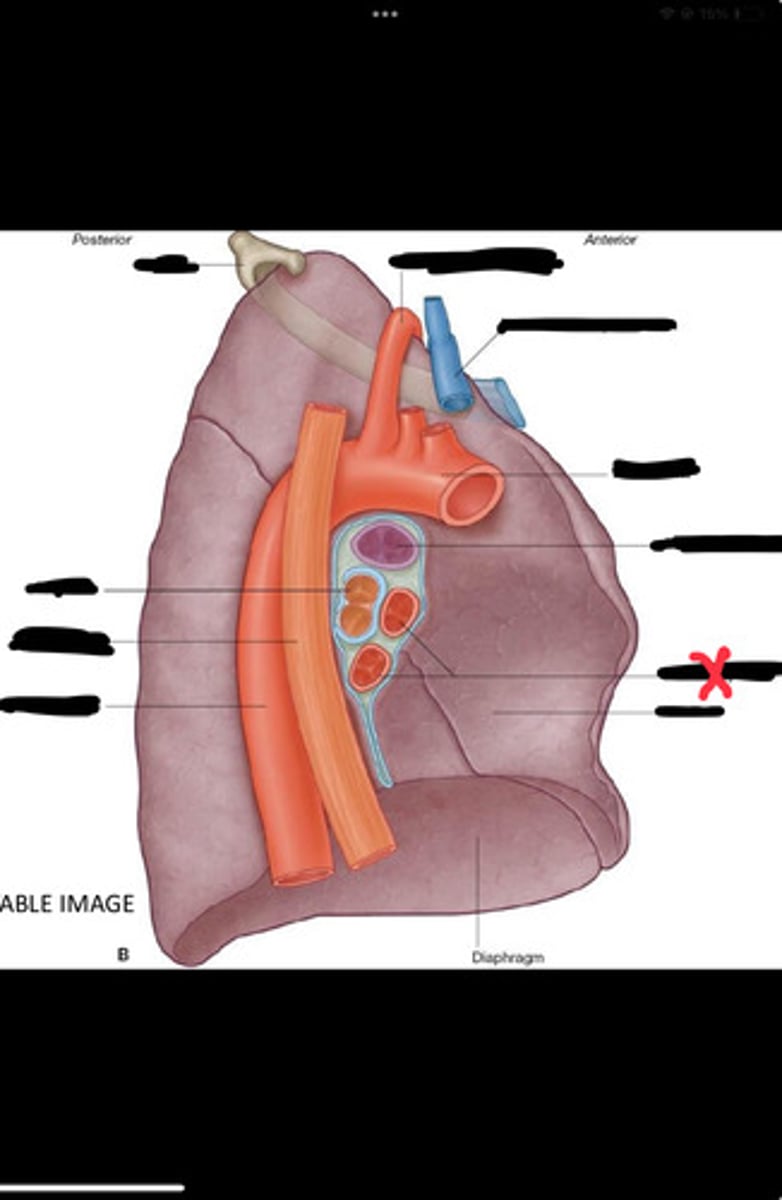

Diaphragm

Inferior vena cava

Superior vena cava

Subclavian vein

Right bracheocephalic vein

Subclavian artery

Esophagus

Bronchus

Rib 1

Left subclavian artery

Left brachiocephalic vein

Aortic arch

Pulmonary artery

Pulmonary vein

Heart

Left brachiocephalic vein

Azygos vein

Esophagus

Bronchus

Fibrous pericardium

Parietal layer of serous pericardium

Pericardial cavity

Visceral layer of serous pericardium

Junction between fibrous pericardium and adventitia

Heart

Thoracic aorta

Rib 1

Pulmonary artery

Bronchus to superior lobe